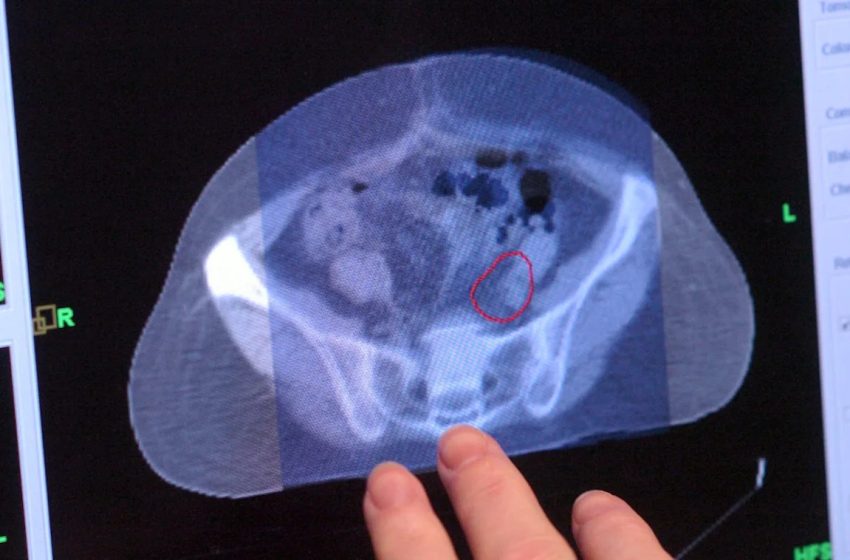

Death rates from colorectal cancer, however, have increased in younger adults, and was the leading cause of cancer death among people under 50 in 2023.

“While we await answers for why colorectal cancer rates are up, lives can be saved now,” said Siegel, the lead author of the report. She noted the need for symptom awareness and more screening uptake, as three in four people under 50 are diagnosed with advanced disease.